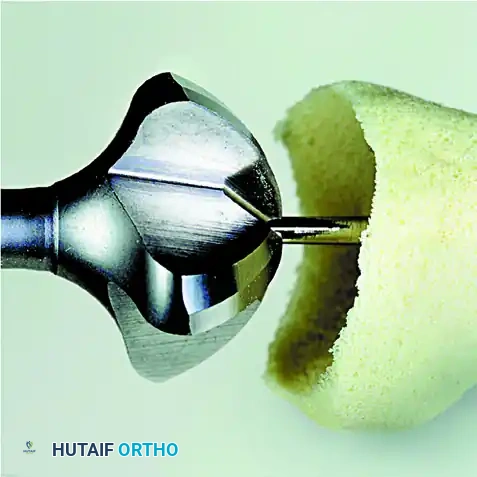

Commercial Reamer Technique (Preferred): Alternatively, and more commonly in modern practice, utilize a commercially available MTP joint cone-arthrodesis system.

First, place a guide pin proximally through the center of the metatarsal head, directing it down the anatomical axis of the diaphysis using a wire driver. Pass the largest female (concave) reamer over the guide pin and gently ream the metatarsal head.

Use progressively smaller reamers until the appropriate size is reached to remove the entire articular surface, exposing healthy, bleeding subchondral bone. Note the size of the final female reamer used.

Gently ream the base of the proximal phalanx starting with the smallest male (convex) reamer. Progress through the reamer sizes until the matching size reamer (corresponding to the final metatarsal reamer) has been used.

The articular surfaces should now be perfectly congruent, allowing significant freedom of motion to dial the hallux into the exact appropriate position for fusion.